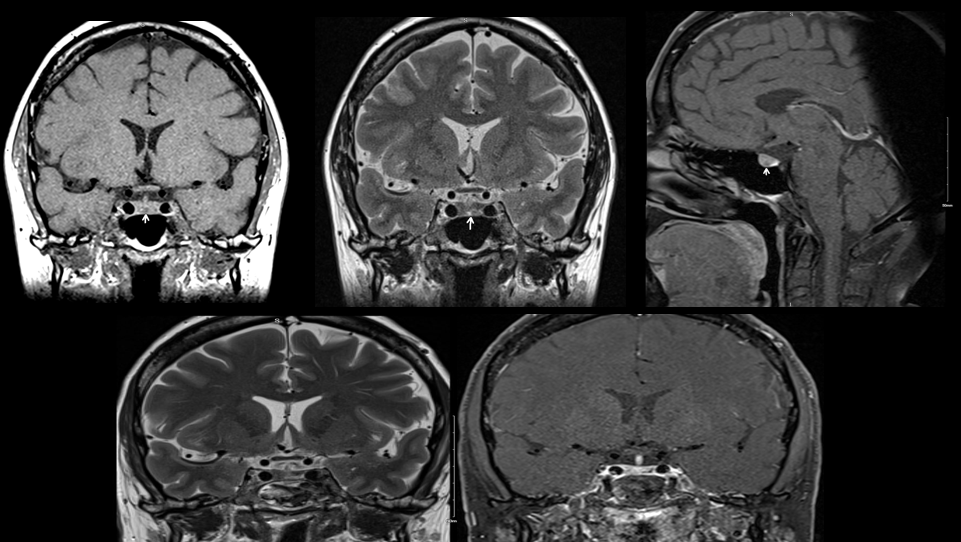

Background

This study explored whether Myelin Water Imaging could detect myelin injury in Anti-NMDA receptor autoimmune encephalitis (NMDAr-AIE), where traditional neuroimaging is often normal. Myelin Water Fraction (MWF) quantifies myelin content by distinguishing myelin sheath water from other brain water compartments.

Methods

Adult participants with confirmed NMDAr-AIE diagnoses and healthy controls (HC) underwent 3T brain MRI (Magnetic Resonance Imaging) including MWF mapping. Participants were recruited after discharge from the hospital. Mean MWF was calculated for 4 white matter regions of interest (ROI). MHI (Myelin heterogeneity Index) was calculated by dividing the MWF standard deviation by the mean MWF. Patient demographics, clinical assessments, treatment, and outcomes were collected.

Results

Five participants with NMDAr-AIE (4F/1M, mean age 30, SD 7) and four HC (3F/1M, mean age 36, SD 6) were included. All NMDAr-AIE participants had normal or non-specific T2 hyperintensities on initial imaging and had received immunotherapy. The mean Modified Rankin Score (MRS) on discharge was 2. MWF (mean ± SD) for normal-appearing white matter, corpus callosum, corticospinal tract, and superior longitudinal fasciculus were 0.10±0.02, 0.12±0.02, 0.15±0.03, 0.12±0.02, which were very similar to HC at 0.09±0.02, 0.11±0.01, 0.15±0.02, and 0.11±0.02, respectively.

Fig. 1 Myelin Water Imaging of two selected patients

Screenshot 2025 06 01 at 12.05.23 pm

Conclusions and Future Direction

Myelin Water Imaging showed no myelin pathology in five NMDAr-AIE patients, with MWF and MHI values comparable to HC, suggesting that myelin pathways are relatively preserved post-recovery from AIE. Moving forward, we aim to continue recruiting healthy controls, patients post-recovery and those experiencing active disease to determine if there are any MWF abnormalities throughout the disease course. Future studies are needed to assess MWF changes in other antibody-mediated encephalitides.